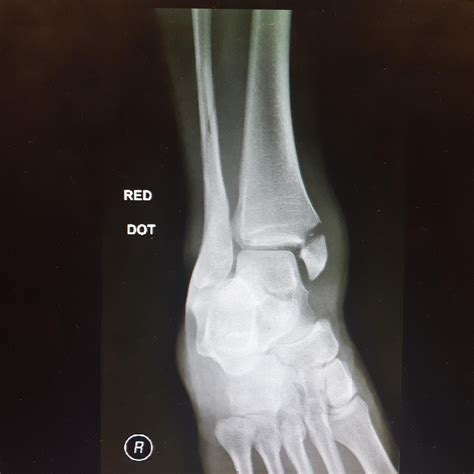

A doctor will typically start by physically examining the foot and ordering imaging tests. An X-ray is the standard tool to confirm a top broken foot, though in some instances of stress fractures, an MRI or CT scan may be necessary to see the damage more clearly.

• top of foot broken pictures